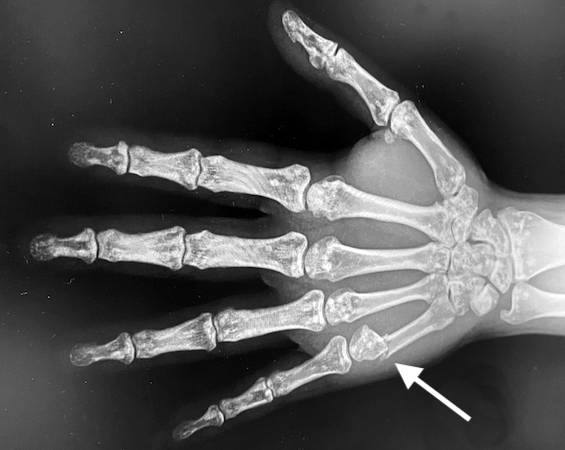

• Osteopoikilosis right hand AP X-ray with a Boxer's fracture (arrow)

Osteopoikilosis right hand AP X-ray with a Boxer's fracture (arrow)